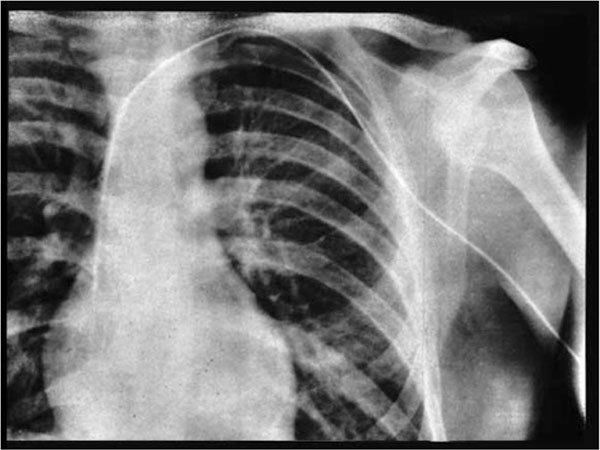

Ambiţiosul medic a fost de acord, a anesteziat-o pe femeie şi, când a fost sigur că aceasta doarme, şi-a introdus singur un cateter în venă, până la inimă, realizând astfel procedura pe care o dorea. Ca să arate că este cu adevărat posibil, le-a prezentat colegilor, ulterior, o radiografie care arăta cum a ajuns cu acel cateter la inimă.